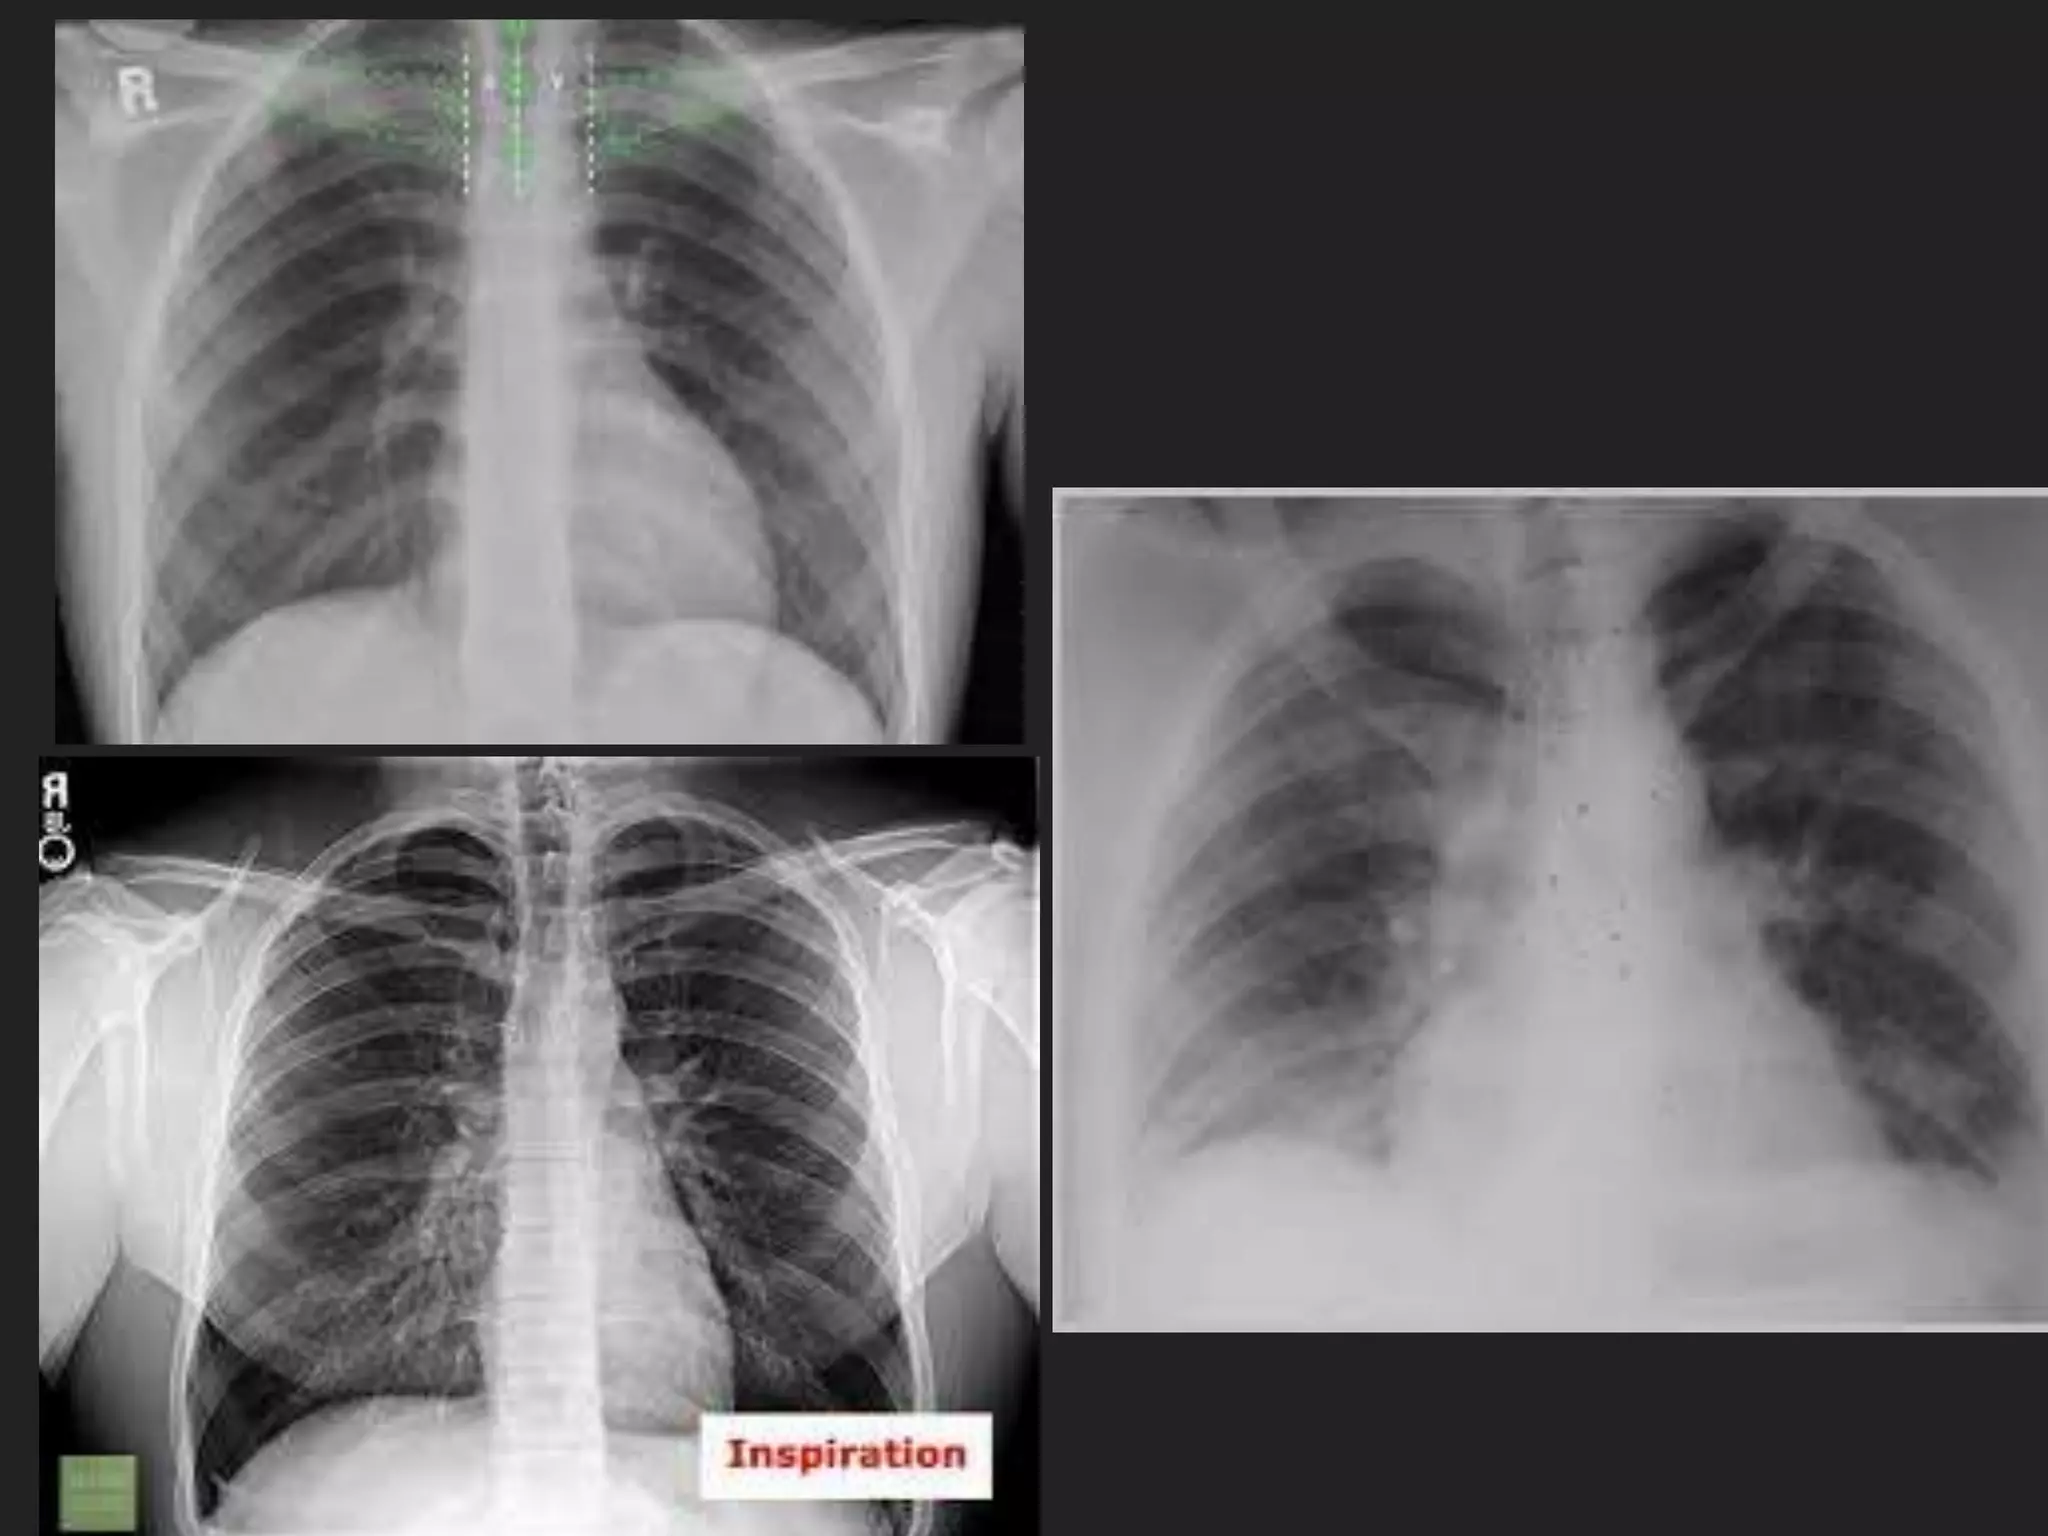

The document provides detailed instructions for performing a chest x-ray, emphasizing proper patient positioning and technical requirements for optimal image quality. Key points include centering the trachea, ensuring full inspiration, and visibility of specific anatomical features. Additionally, it outlines collimation margins and patient stance to achieve a clear view of lung fields.